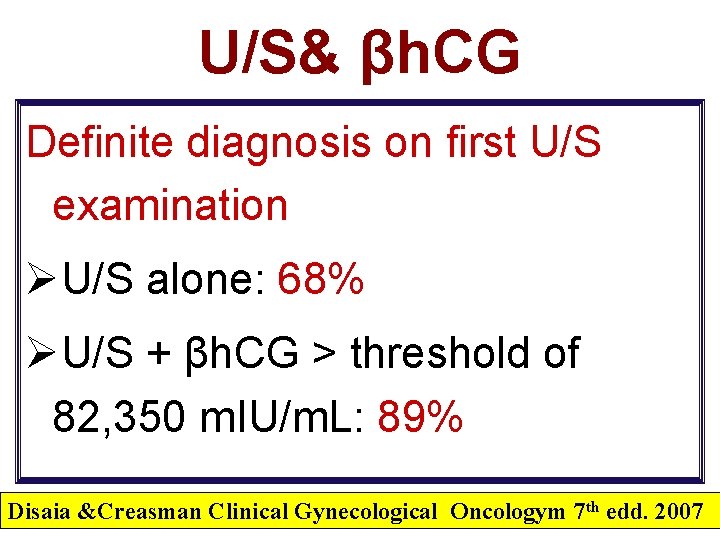

TVS “Milestones” Versus βh. CG m. IU/m. L Weeks Detection Level >5 3 -4 Choriodecidual thickening 100 Gestational sac (D Zone) 1000 -1500 Yolk sac Heart motion 7000 4 4 -5 5 - 6 10, 000 6 Embryonic Movem. > 10. 000 6 - 7 Maximum level 50, 000 to 100, 000 8 -10